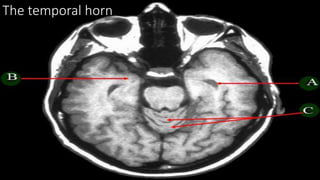

THE VENTRICLES

Ventricles

• Lateral ventricle

• Frontal horn

• Occipital horn

• Temporal horn

• Third ventricle

• Fourth ventricle

• Central canal

Foramen monoro

Aqueduct of Silvius

Interventricular foramina

(or foramina of monro)

The lateral ventricle

The frontal horn

The

occipital

horn

The temporal horn

The 3rd ventricle

The 4th ventricle

Foramen Luschka and Magendie